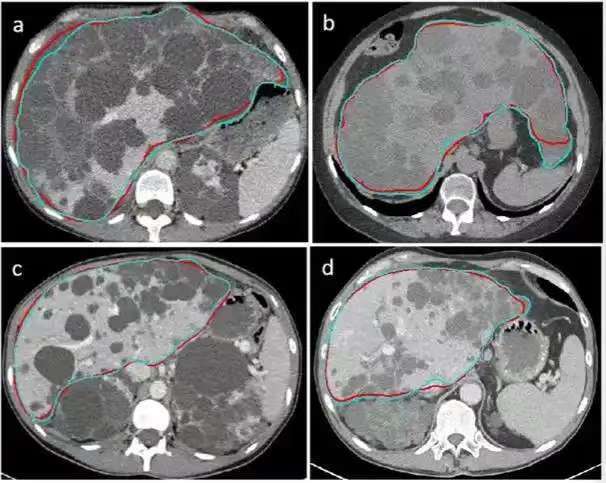

多囊肝?。ˋPLD)是一種遺傳性疾病,以肝臟多發(fā)散在的囊腫為特征,常常伴有多囊腎。早期無(wú)明顯臨床癥狀,隨著囊腫進(jìn)展,肝臟體積增大,可出現(xiàn)腹痛,腹脹、惡心、嘔吐等臨床表現(xiàn)[1,2]。目前,多囊肝病的臨床治療復(fù)發(fā)率高,并發(fā)癥多,效果不甚理想,而且臨床上沒(méi)有統(tǒng)一的治療方法[3]。我科在國(guó)際上首次對(duì)多囊肝病患者實(shí)施了超聲引導(dǎo)下射頻消融治療,已成功完成13例,充分證明了經(jīng)皮射頻消融治療多囊肝病的有效性及安全性。 1資料與方法 一般資料 本研究回顧性分析2018年1月-2019年12月在我科接受射頻消融治療的14例多囊肝病患者,其中,男性4例,女性10例,年齡35-64(51±8)歲。14例多囊肝患者的臨床資料如下(見(jiàn)表1)。14例患者均經(jīng)肝臟增強(qiáng)CT或增強(qiáng)MRI確診為多囊肝病,且引起臨床癥狀,如腹脹、腹部隱痛等。肝功能Child-Pugh分級(jí)A級(jí)。凝血功能正常,無(wú)其他全身性感染等禁忌癥。 1.2 儀器與設(shè)備 采用綿陽(yáng)立德公司生產(chǎn)的多極射頻消融系統(tǒng)(冷循環(huán)),型號(hào)為L(zhǎng)DRF-120S。超聲設(shè)備為PHILIPS EP IQ7,變頻探頭型號(hào)為C5-1,探頭頻率為1~5MHZ,用于超聲引導(dǎo)治療。 1.3 方法 術(shù)前完善血常規(guī)、凝血功能、肝腎功能、傳染病、心肺功能等檢查。術(shù)前禁食水8 h,酌情行腸道準(zhǔn)備;術(shù)前行超聲檢查,評(píng)估消融范圍及擬定消融進(jìn)針?lè)桨浮J中g(shù)操作:患者平臥位,常規(guī)消毒、鋪無(wú)菌單,全麻(為了盡可能多的消融囊腫,延長(zhǎng)手術(shù)時(shí)間),超聲引導(dǎo)下先行17G消融電極(帶抽吸側(cè)孔)進(jìn)入囊腫內(nèi),待抽凈囊內(nèi)液體后,啟動(dòng)消融設(shè)備,起始功率設(shè)置為150W,進(jìn)行囊壁RFA治療,至囊壁完全被強(qiáng)回聲覆蓋,消融結(jié)束。治療方案(圖1):a.對(duì)于單個(gè)囊腫直徑>5cm或者單個(gè)囊腫2cm<D<5cm且相鄰囊腫直徑之和>5cm,先行射頻電極依次進(jìn)入囊內(nèi),抽凈囊液,待囊壁皺縮至附著于電極,然后啟動(dòng)消融,對(duì)囊腫回縮區(qū)進(jìn)行消融,至囊壁被強(qiáng)回聲覆蓋,消融結(jié)束。b.對(duì)于囊腫直徑<2cm,無(wú)需抽液,射頻電極直接進(jìn)入囊腫聚集區(qū),啟動(dòng)消融,至囊腫及囊壁被強(qiáng)回聲覆蓋,消融結(jié)束。若有足夠正常肝實(shí)質(zhì)代償情況下,盡可能多的消融囊腫。若沒(méi)有足夠正常肝實(shí)質(zhì)代償,對(duì)于此類(lèi)小囊腫可達(dá)到a中標(biāo)準(zhǔn)時(shí)再做處理。 1.4 療效評(píng)價(jià) 觀察術(shù)后并發(fā)癥(出血、膽瘺、腹水等);平均住院時(shí)間;比較射頻消融治療前與治療后12個(gè)月患者肝內(nèi)囊腫總體積(使用CT機(jī)的 Volume測(cè)量軟件對(duì)囊腫體積進(jìn)行測(cè)量并記錄);檢測(cè)治療前與治療后1周肝功能(ALT,AST,TBIL),評(píng)價(jià)射頻消融治療對(duì)肝功能的影響。 1.5 統(tǒng)計(jì)學(xué)分析 應(yīng)用SPSS 21.0 軟件進(jìn)行統(tǒng)計(jì)分析,計(jì)量單位以均數(shù)±標(biāo)準(zhǔn)差((X±S)表示,比較射頻消融治療前與治療后12個(gè)月肝內(nèi)囊腫總體積,射頻消融治療前與治療后1周肝功能改變,采用配對(duì)t檢驗(yàn),P<0.05為差異有統(tǒng)計(jì)學(xué)意義。 2 結(jié)果 2.1 射頻消融后并發(fā)癥等情況 1例患者因術(shù)中出血,終止治療。余13例多囊肝患者射頻消融治療后即刻囊腔消失、肝內(nèi)囊腫總體積縮小。術(shù)后腹脹較術(shù)前明顯好轉(zhuǎn)。術(shù)后第1d,3例患者出現(xiàn)上腹部輕度疼痛,疼痛評(píng)分4級(jí)(考慮術(shù)后反應(yīng)),給予保肝、抗炎等處理,腹部疼痛較前好轉(zhuǎn),2例患者自訴夜間惡心嘔吐,無(wú)其他不適,給予患者營(yíng)養(yǎng)支持、補(bǔ)液等對(duì)癥處理,癥狀好轉(zhuǎn),余8例患者無(wú)其他不適。術(shù)后1周,癥狀明顯緩解率為92.31%(12/13)?;颊咂骄≡海?±2)d。術(shù)后12個(gè)月,1例患者因肝內(nèi)最大囊腫囊壁未消融完全,囊腫復(fù)發(fā)。 2.2 比較射頻消融治療前與治療后12個(gè)月患者肝內(nèi)囊腫總體積 射頻消融治療12個(gè)月后肝內(nèi)囊腫總體積與治療前相比,治療前的囊腫總體積為(2573.35~5960.11)cm3,平均值為(4068.91±1145.11)cm3 ,治療后12個(gè)月為(1305.70~2862.23)cm3,平均值為(2027.17±584.70)cm3,采用配對(duì)t檢驗(yàn),t=9.259, P<0.05,差異有統(tǒng)計(jì)學(xué)意義(見(jiàn)表 2)。13例肝內(nèi)囊腫總體積縮小率26.33%~63.03%,平均(49.60±10.04)%。 2.3檢測(cè)射頻消融治療前與治療后1周肝功能(ALT,AST,TBIL),評(píng)價(jià)射頻消融治療對(duì)肝功能的影響 13例多囊肝患者射頻消融治療前與治療后1周的 ALT、AST、TBIL均無(wú)顯著差異(P>0.05)(見(jiàn)表3),射頻消融對(duì)患者肝功能影響較小。 3 討論 臨床上治療多囊肝病的常用方法有超聲引導(dǎo)下囊腫穿刺抽液及硬化治療,腹腔鏡下或開(kāi)腹開(kāi)窗去頂術(shù),肝部分切除術(shù),肝切除聯(lián)合囊腫開(kāi)窗以及肝移植等。但是這些治療方法存在不同程度的缺陷[4,5]。如囊腫抽液及硬化治療,缺點(diǎn)其一是酒精過(guò)量會(huì)致使酒精中毒;其二是囊壁沖洗不干凈,致使硬化劑不能充分接觸囊壁,囊壁毀損不完全,容易導(dǎo)致復(fù)發(fā),常需要多次引流及硬化治療;長(zhǎng)期后果是肝臟組織纖維化,抽液減壓后,囊腫不易回縮[6,7]。囊腫開(kāi)窗術(shù)僅適用于靠近肝表面的囊腫,位置較深的囊腫無(wú)法開(kāi)窗,因此,單純的囊腫開(kāi)窗不能有效治療多囊肝病[8]。肝葉切除可使癥狀消失,復(fù)發(fā)率低,但術(shù)后并發(fā)癥發(fā)生率較高,其中最多見(jiàn)腹水、胸腔滲液、肝功能衰竭、膽漏等,臨床很少采用[9]。肝切除聯(lián)合囊腫開(kāi)窗可彌補(bǔ)單純囊腫開(kāi)窗不足,對(duì)深部囊腫進(jìn)行肝部分切除,可在緩解癥狀的同時(shí),有效縮小肝體積,但也帶來(lái)了手術(shù)所造成的相應(yīng)并發(fā)癥如腹水,胸腔積液,膽漏等[10]。唯一有效的肝移植治療,病人需終身免疫治療,尚且考慮到肝供體缺乏,風(fēng)險(xiǎn)大,費(fèi)用高,臨床慎用[11,12]。因此,對(duì)于多囊肝患者,探究一種新型有效治療方法,能夠減小肝內(nèi)囊腫總體積、減少術(shù)后并發(fā)癥、降低術(shù)后復(fù)發(fā)率、提高患者遠(yuǎn)期生存率及生活質(zhì)量,具有重要的臨床意義。 近年來(lái),射頻消融在治療實(shí)體腫瘤方面已廣泛開(kāi)展,療效確切,顯示了其創(chuàng)傷小、安全性高、可重復(fù)應(yīng)用等優(yōu)勢(shì)[13,14]。張慶帥等[15]報(bào)道射頻消融治療復(fù)發(fā)性肝囊腫,取得了良好臨床效果。本研究團(tuán)隊(duì)前期成功射頻消融治療了多例卵巢癌肝內(nèi)多發(fā)轉(zhuǎn)移患者,部分肝轉(zhuǎn)移以囊性或混合性形式存在,這些臨床經(jīng)驗(yàn)為射頻消融治療多囊肝病提供了新思路。射頻消融通過(guò)電極發(fā)射頻繁變化的高頻交變電流,使組織細(xì)胞內(nèi)的導(dǎo)電離子或極化分子快速變換方向,相互振蕩,摩擦產(chǎn)生熱能,導(dǎo)致局部溫度達(dá)100℃左右,使組織細(xì)胞迅速發(fā)生蛋白變性并產(chǎn)生不可逆凝固壞死,從而達(dá)到治療目的。多囊肝病是源于與膽道系統(tǒng)脫離的膽管上皮細(xì)胞過(guò)度擴(kuò)增和過(guò)度分泌,形成肝內(nèi)大小不等的多發(fā)囊腫。本研究利用射頻消融的熱效應(yīng),使囊腫內(nèi)壁細(xì)胞凝固發(fā)生不可逆壞死,毀損囊壁,失去分泌能力,囊壁毀損致使囊腫復(fù)發(fā)的基礎(chǔ)不復(fù)存在。相對(duì)于傳統(tǒng)的開(kāi)窗去頂術(shù)及切除手術(shù),射頻消融治療對(duì)周?chē)M織損傷小,降低術(shù)后并發(fā)癥。本研究亦表明,在保證有足夠正常肝實(shí)質(zhì)代償條件下,實(shí)施射頻消融治療,對(duì)肝功能幾乎沒(méi)有影響。 本研究14例多囊肝患者,13例成功完成消融治療,1例患者因術(shù)中出血終止治療。術(shù)后1周,癥狀明顯緩解率為92.31%(12/13),肝功能正常。術(shù)后12個(gè)月,12例患者肝內(nèi)囊腫總體積明顯縮小,肝功能均正常;1例患者因最大囊腫囊壁毀損不完全,囊腫增大。筆者認(rèn)為,選擇合適的病例及合理的消融布針?lè)桨甘墙档托g(shù)后并發(fā)癥及消除復(fù)發(fā)因素的關(guān)鍵。射頻消融治療多囊肝的關(guān)鍵點(diǎn):①穿刺抽液過(guò)程中,避免囊腔壓力驟減引起出血,應(yīng)緩慢抽吸。②對(duì)于大于5cm的囊腫,直接先行抽凈囊液,后啟動(dòng)消融,毀損囊壁,致使囊腫復(fù)發(fā)基礎(chǔ)不復(fù)存在。對(duì)于小于2cm的囊腫,有潛在長(zhǎng)大的復(fù)發(fā)因素,直接啟動(dòng)消融損毀,徹底消除復(fù)發(fā)因素,避免以后復(fù)發(fā),有望達(dá)到臨床徹底治愈。③術(shù)中根據(jù)肝內(nèi)囊腫數(shù)目、大小及分布范圍等,必要時(shí)調(diào)整消融電極的位置及方向,實(shí)現(xiàn)1個(gè)穿刺點(diǎn)消融盡可能多的囊腫,以達(dá)到微創(chuàng)、安全的目的。 綜上所述,射頻消融治療多囊肝病創(chuàng)傷小,恢復(fù)快,囊腔即刻消失、迅速緩解癥狀,能夠減少并發(fā)癥及降低復(fù)發(fā)率,因此,射頻消融治療多囊肝是一種安全有效的新型治療方法。由于本組樣本量少、隨訪時(shí)間短,所以還需進(jìn)一步的臨床研究,以確保其安全、有效。